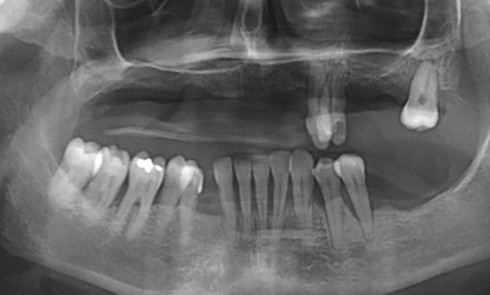

L’implant est devenu un outil incontournable de nos plans de traitement de réhabilitation orale. La codification des phases d’élaboration prothétique...